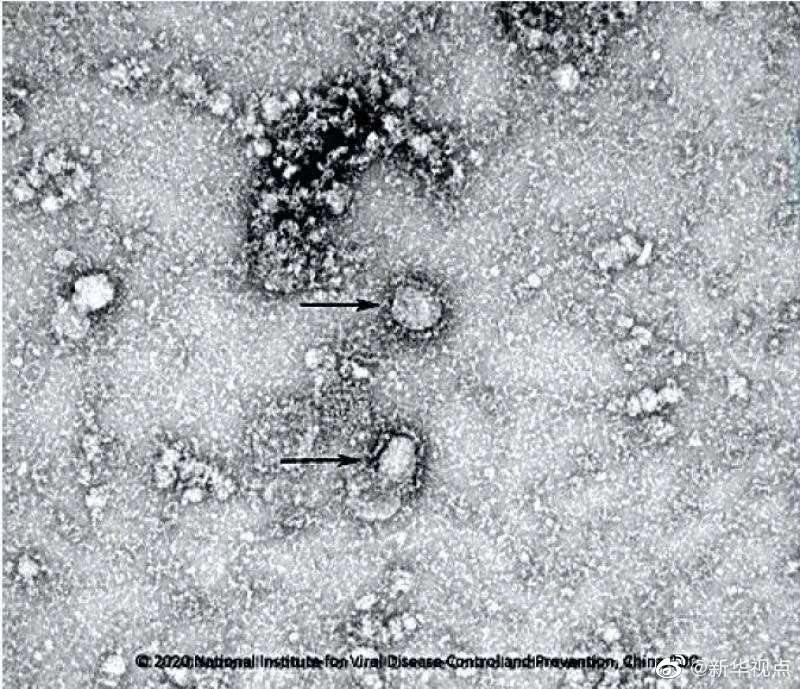

國家病原微生物資源庫于2020年1月24日發布了由中國疾病預防控制中心病毒病預防控制所成功分離的我國第一株病毒毒種信息及其電鏡照片、新型冠狀病毒核酸檢測引物和探針序列等國內首次發布的重要權威信息,并提供共享服務。看病毒“真容”↓↓↓(記者田曉航、王秉陽)

好消息!中國疾控中心成功分離我國首株新型冠狀病毒毒種,它長這樣!-新華網